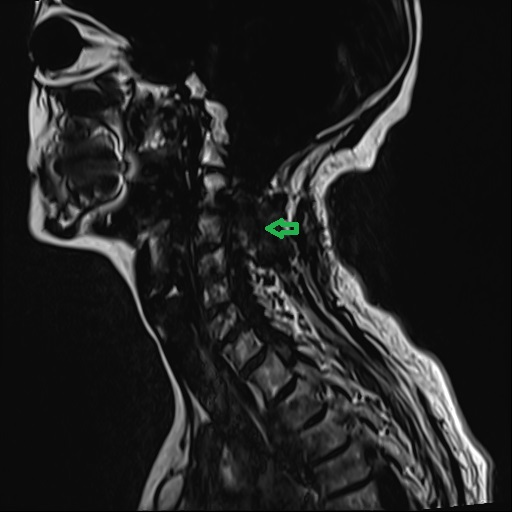

据悉,患者赵婆婆(化名)今年已70岁,日前因反复头晕且有加重趋势前来医院治疗,行头部和颈部核磁检查发现颈2-3右侧椎间孔区占位病变,考虑肿瘤性病变。神经外科医疗团队迅速研究治疗方案后,为其进行行了手术治疗,切除了患者的肿瘤。

术前后术后的核磁对比